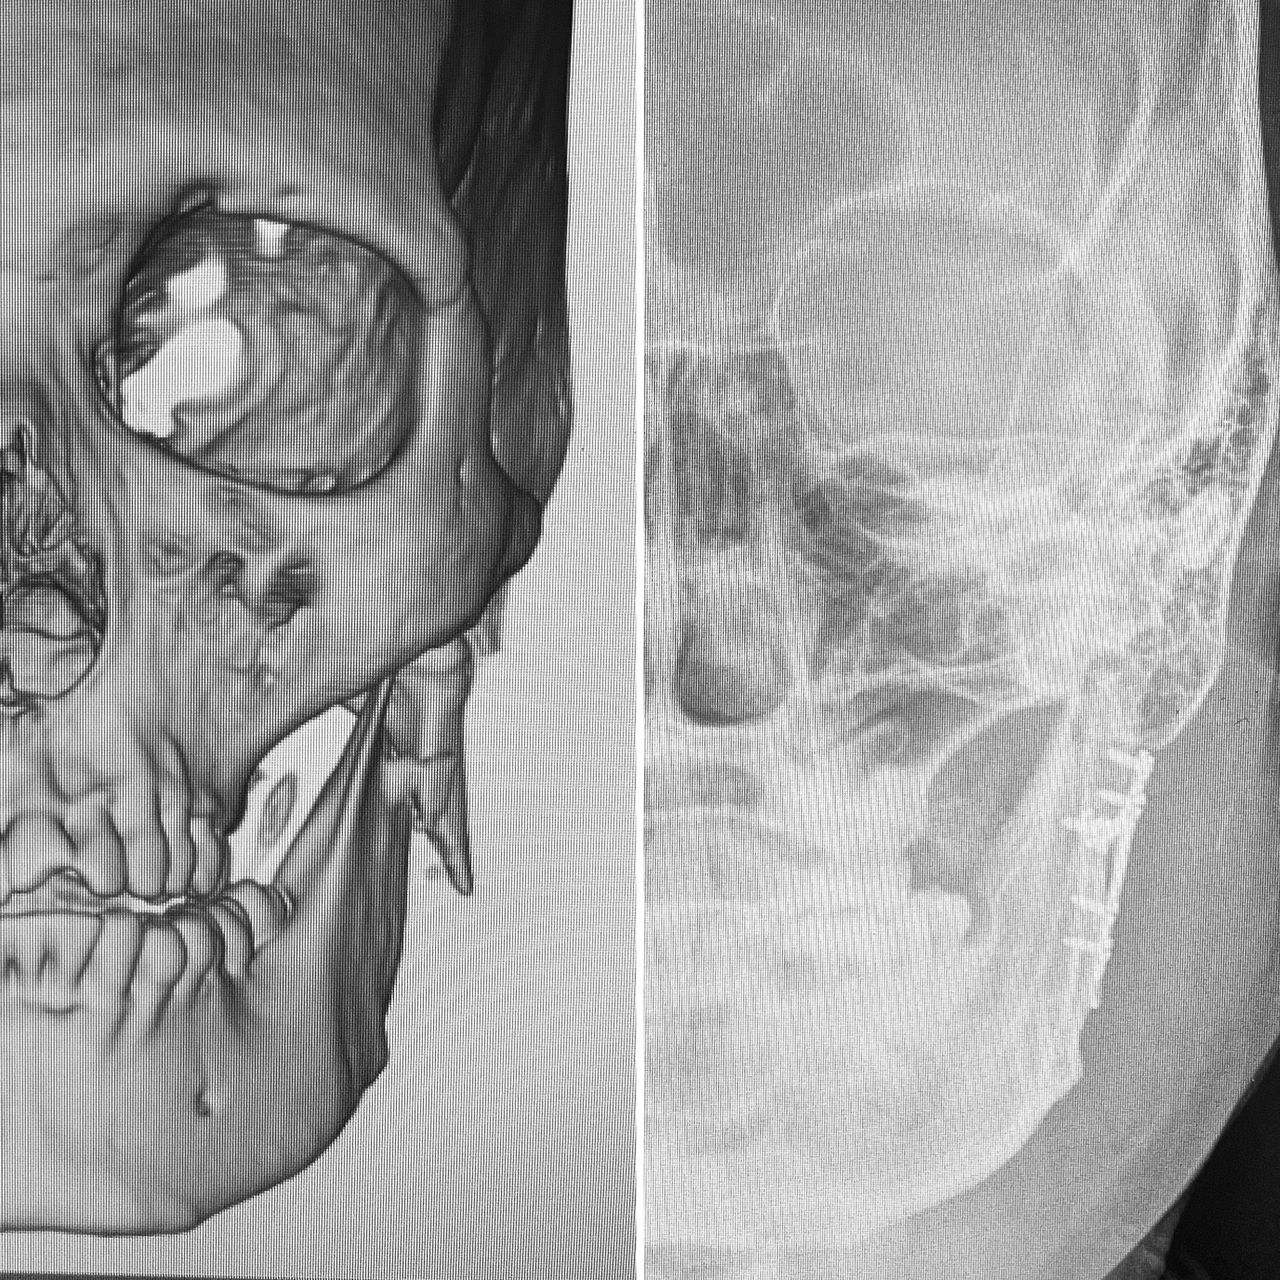

Cuento con experiencia en procedimientos de cirugía oral como: exodoncias simples, exodoncia de dientes incluidos y terceros molares, biopsias, frenillectomias, implantes dentales, implantes cigomáticos, implantes yuxtaoseos, regeneración ósea y tisular guiada.

En el área de cirugía maxilofacial tengo experiencia en el manejo quirúrgico de trauma facial, anomalías dento-faciales, disfunción de articulación temporomandibular, reconstrucción de maxilares, Cirugía estetica Facial, blefaroplastia, otoplastia, mentoplastia, Lifting facial, Lip Lift y reposicionamiento labial, retiro de biopolimeros en cara y Armonización Oro-Facial.

I have experience in oral surgery procedures such as: simple extractions, extraction of impacted teeth and third molars, biopsies, frenectomies, dental implants, zygomatic implants, juxta-osseous implants, and guided bone and tissue regeneration.

In the field of maxillofacial surgery, I have experience in the surgical management of facial trauma, dentofacial anomalies, temporomandibular joint dysfunction, mandibular reconstruction, facial cosmetic surgery, blepharoplasty, otoplasty, mentoplasty, facelifts, lip lifts and lip repositioning, removal of facial biopolymers, and orofacial harmonization.

- Cirugía ortognática